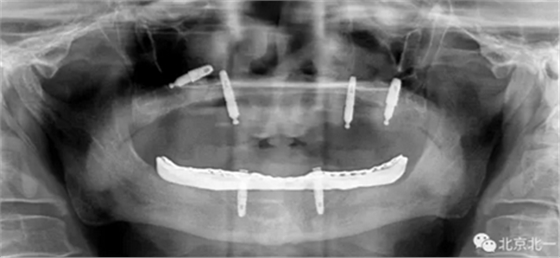

圖二:覆蓋義齒

圖三:植體負重一年后脫落掉入上頜竇,

圖四:王明老師接手時植體往后移位,